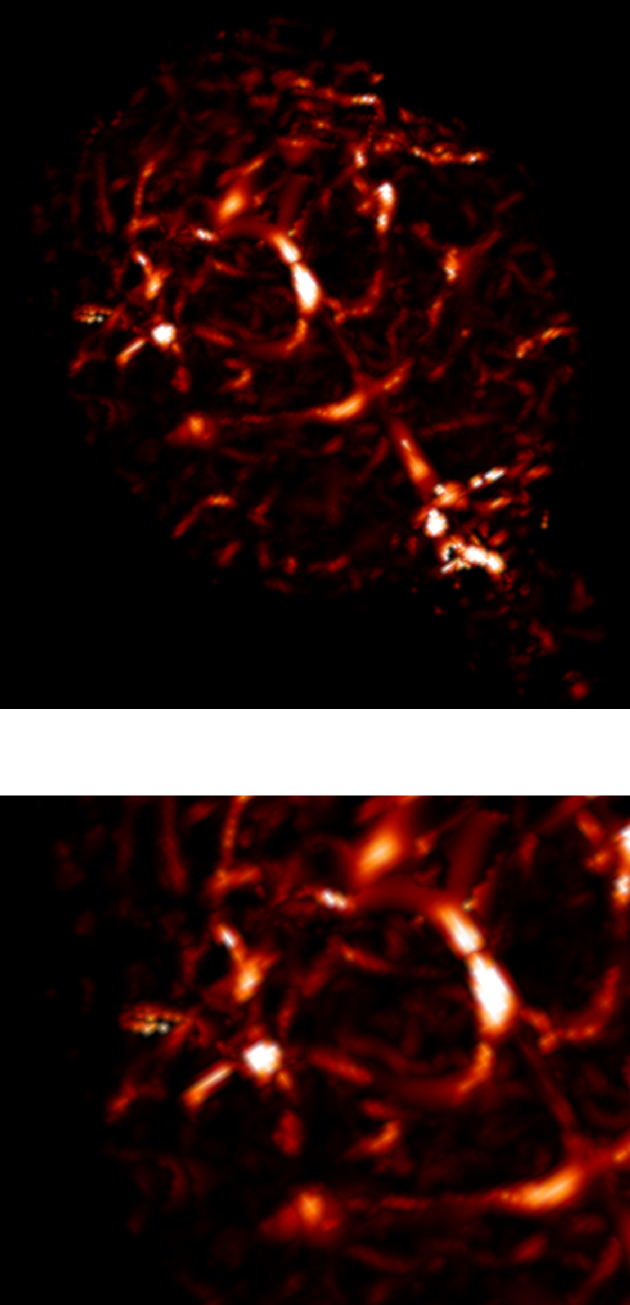

3.2.1 2D reconstructions

In this experiment, we considered a 2D -space () corresponding to an axial slice. We considered five sampling strategies, depicted in Fig. 2(first row): a classical EPI coverage used as reference (a); a TSP-based sampling trajectory parameterized using optimal control (b); two projected TSP-based trajectories, one with the same number of samples collected as in (b) () (c) and the other with the same scanning time as in (b) (62 ms) (d); a variable density spiral trajectory for comparison purpose in terms of time and sampling ratio (e).

As expected, the reconstruction results shown in Fig. 2(g,h) are really close, since the number of collected samples is the same, and the sampling densities are similar. However, in this comparison the gain in traversal time is significant (one half). In contrast, the longer and smoothed TSP depicted in Fig. 2(d) allows us to improve image reconstruction (1 dB gain) as illustrated by Fig. 2(i) while keeping the same acquisition time as in Fig. 2(b). For comparison purposes, we implemented spiral acquisition which consists of replacing steps (ii)-(iii) in the above mentioned sampling strategy by a spiral with density proportional to , projected onto the set of constraints. This strategy doubles the acquisition time (118 ms compared to 62 ms) whereas the acceleration factor was larger ( vs. ). In this experimental context (regridding and variable density spiral), the spiral is not appealing compared to EPI acquisition, since it is time consuming and degrades the image quality.

In each of these reconstructions, the major vessels can be recovered, although the smallest ones can only be seen for . Finally, the best compromise between acquisition time and reconstruction quality is achieved using the specific combination of TSP-based sampling and our projection algorithm onto the set of constraints shown in Fig. 2(d).

| (a) | (b) | (c) | (d) | (e) |

|---|---|---|---|---|

|

Sampling schemes

![]() |

| ms () | ms () | ms () | ms () | ms () |

| (f) | (g) | (h) | (i) | (j) |

Reconstructed slices

| Reference | PSNR = 25.9 dB | PSNR = 25.5 dB | PSNR = 26.9 dB | PSNR = 26.8 dB |